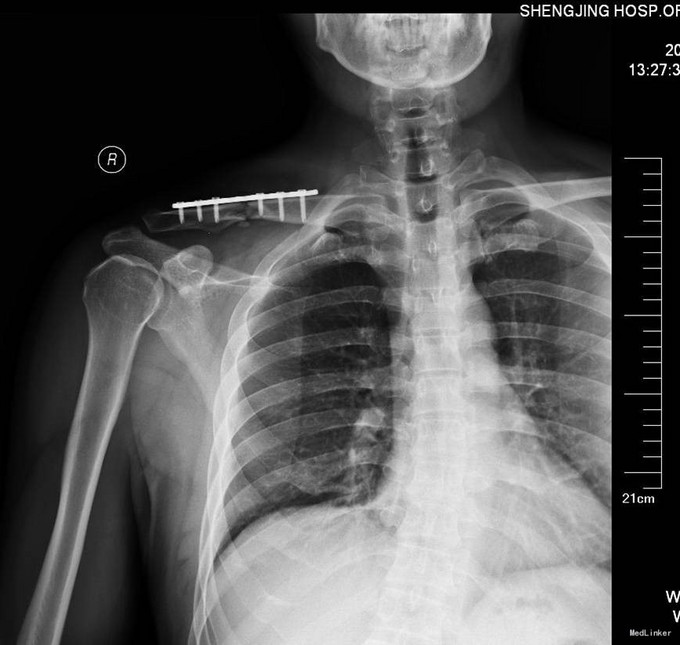

患者入院后完善相关生化检查,完善胸片及心电图等,查无明显手术禁忌症后急诊全麻下行左锁骨骨折切开复位内固定术。术后患者第二天退院。